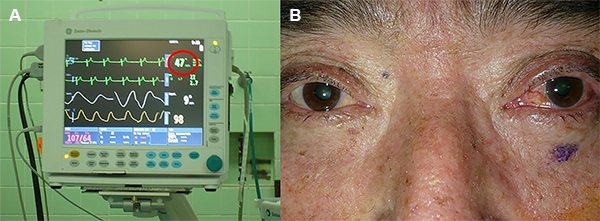

Dosis de 0.5 mg de atropina por vía intravenosa fue administrada cuando ocurrió reducción de más de 20% de frecuencia cardíaca basal, durante la punción del foramen oval o durante la compresión con el balón. Sólo en pacientes con tendencia a la bradicardia se le administró previamente atropina. No colocamos marcapaso externo.

Durante la punción del agujero oval o durante la compresión con el balón se observó una respuesta trigeminal depresora que consiste en bradicardia con breve hipotensión arterial, seguida de una hipertensión refleja (Figura 8A). Asimismo, se observó un movimiento de contractura del masetero, es decir una mordida. La inyección conjuntival ipsilateral al procedimiento se debió al compromiso temporal de la función neurovegetativa (Figura 8B). Todo el procedimiento generalmente duró menos de 15 minutos.